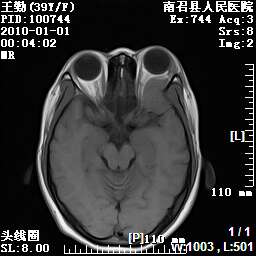

以下是引用随光逐影在2010-1-22 9:03:00的发言:[br]考虑左侧中颅窝(蝶骨翼区)脑膜瘤侵犯蝶骨翼并突入左侧眼眶。

以下是引用水过无痕在2010-1-22 14:55:00的发言:[br]一、定位:颅外占位;二、定性:恶性可能性大;三、组织来源:来源于左侧眼外直肌或其他部位;考虑为:横纹肌肉瘤>转移瘤>脑膜瘤.